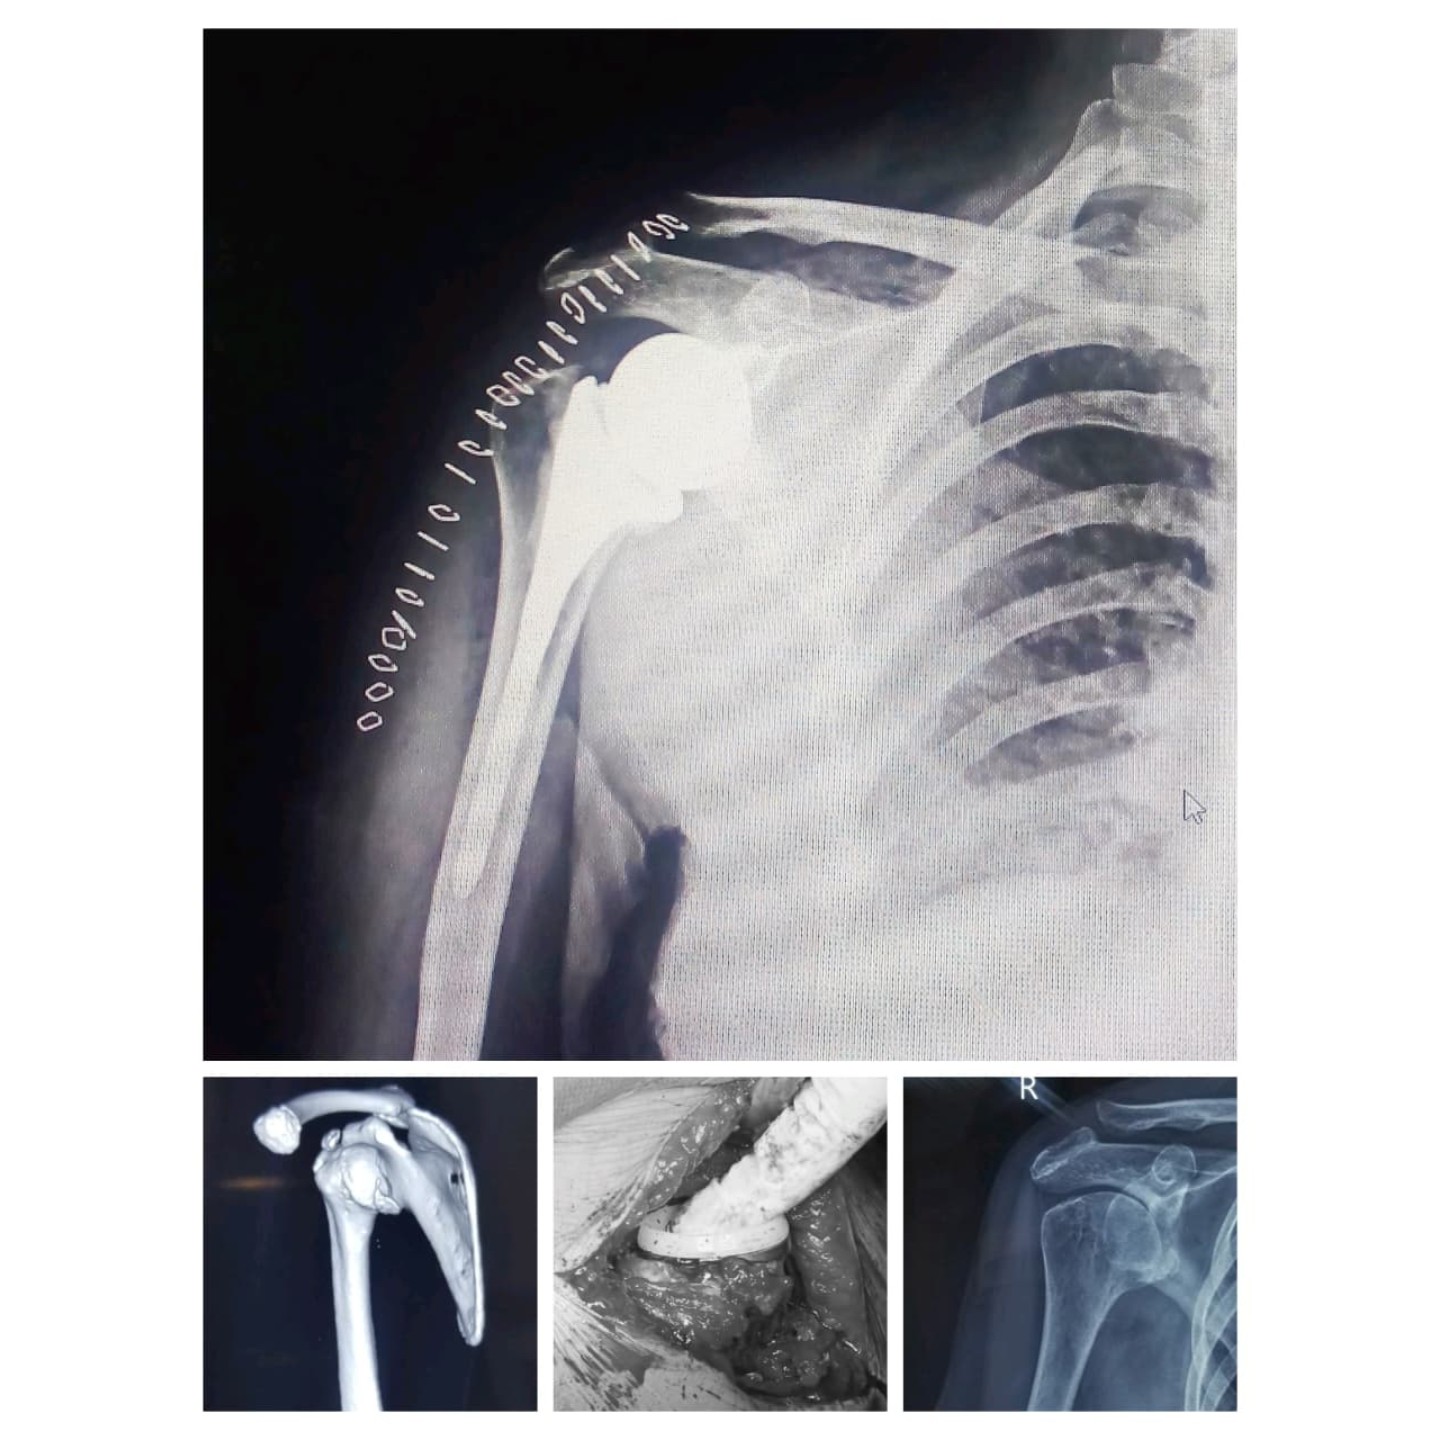

Reverse total shoulder arthroplasty

Anatomical Total shoulder arthroplasty